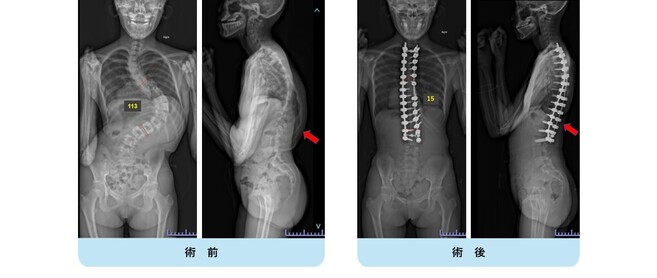

思春期特発性側弯症が高度に進行した症例です。最大側弯角度は113°であり、100°を超える側弯の手術は一般的に神経合併症が危惧されます。神経合併症を極力防ぐため、また侵襲を低減する目的で、同じ入院期間に2回に分けて段階的に矯正手術を行いました。1回目に最も側弯の強い箇所に対して側方から椎体間解離を行い、2回目に後方から全体のバランスが良くなるように慎重に矯正固定術を施行しています。

神経合併症はなく、術後の最大側弯角度は15°に改善(矯正率:87%)、背中の大きなコブも無くなっているのが分かります。(赤色矢印)

神経合併症が発生しないように慎重に手術を行うのは当然ですが、側弯を治すだけでなく横から見た姿勢を治すことにも留意しています。